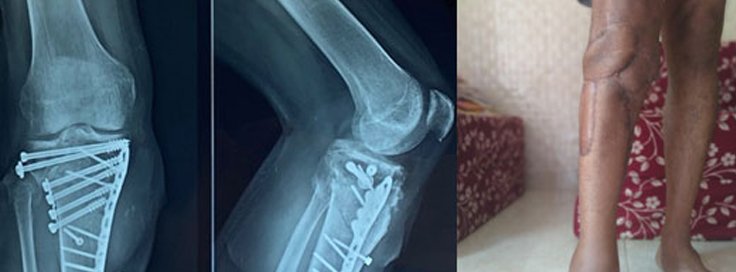

Complicated Knee Fractures Treatment

A complicated knee fracture is a severe injury involving multiple bone fragments, ligament damage, or joint misalignment. Unlike simple fractures, these injuries require specialized treatment to restore function and prevent long-term complications. Knee fracture treatment varies based on severity, with some cases requiring surgery and extensive rehabilitation.

A knee fracture specialist conducts a thorough evaluation using:

• X-rays, to determine the extent of bone damage.

• Knee fracture surgery, such as open reduction and internal fixation (ORIF).